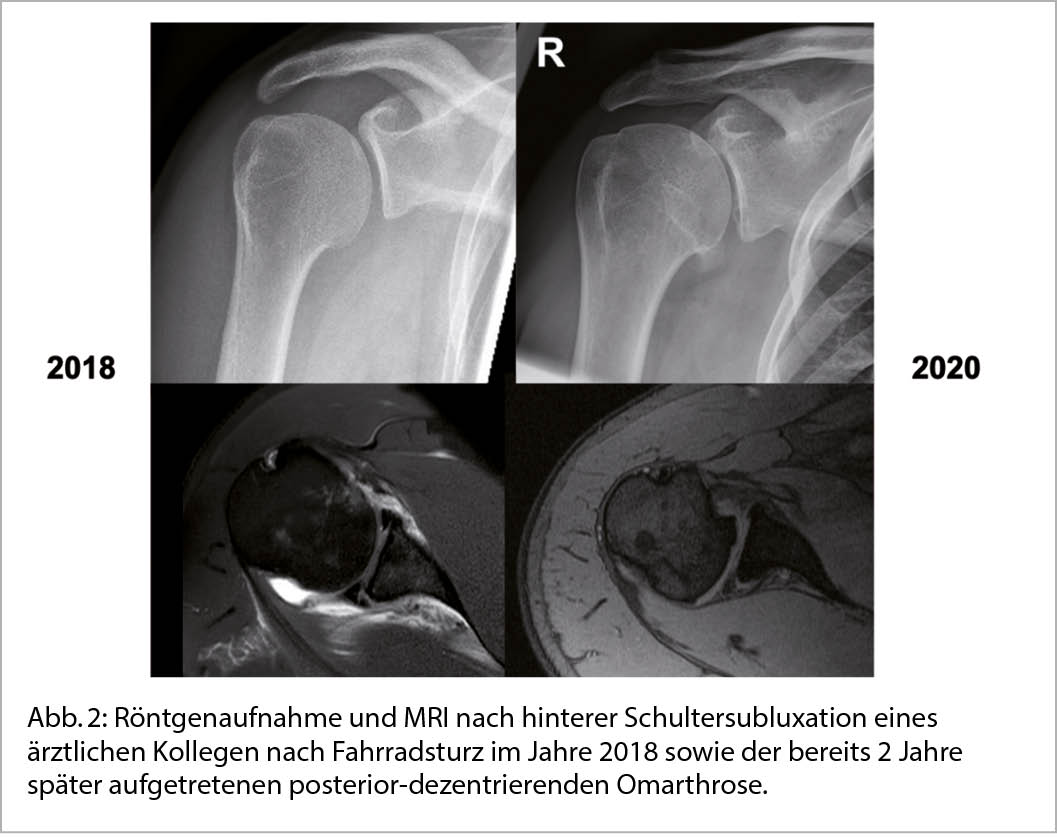

Ist die konservative Therapie ausgeschöpft kann durch die Implantation einer Schulterendoprothese eine zuverlässige Verbesserung der Beschwerden erreicht werden. Die Indikationen zur operativen Versorgung besteht bei therapieresistenten Schmerzen oder unzureichend kompensierbaren Einschränkungen des Bewegungsausmasses sowie zunehmendem Leidensdruck der Patienten. Eine endoprothetische Versorgung kann als anatomische (Total)endoprothese (aTSA) unter Erhalt der ursprünglichen Anatomie oder als inverse Totalendoprothese (rTSA) zur Stabilisierung des Drehzentrums erfolgen (Abb. 4) (12).

Wichtige Strukturen, die zur Zentrierung des Humeruskopfes beitragen sind knöchern die Schultergelenkspfanne sowie weichteilig die Muskeln und Sehnen der Rotatorenmanschette. Exzentrische Omarthrosen aufgrund einer schwerwiegenden Pfannendeformität und statischer Dezentrierung des Oberamkopfes oder aufgrund einer Rotatorenmanschetteninsuffizienz mit instabilem Gelenksdrehzentrum sprechen für die Implantation einer inversen Schulterendoprothese. Der Anteil der implantierten inversen Endoprothesen ist in den letzten Jahren aufgrund der vielfältigen Indikationserweiterungen und nicht zuletzt aufgrund der sehr guten und verlässlich erzielbaren Ergebnisse kontinuierlich gestiegen. Während die inverse Endoprothese durch das stabilere Drehzentrum überzeugt, ist bei der anatomischen Endoprothese das durchschnittlich zu erwartende postoperative Bewegungsausmass grösser. Bei Verlust der Stabilität des Drehzentrums im Verlauf nach Implantation einer anatomischen Schultertotalendoprothese aufgrund einer sekundären Rotatorenmanschetteninsuffizienz oder eines zunehmenden exzentrischen Pfannenabriebes ist der Wechsel auf eine inverse Prothese möglich (13).